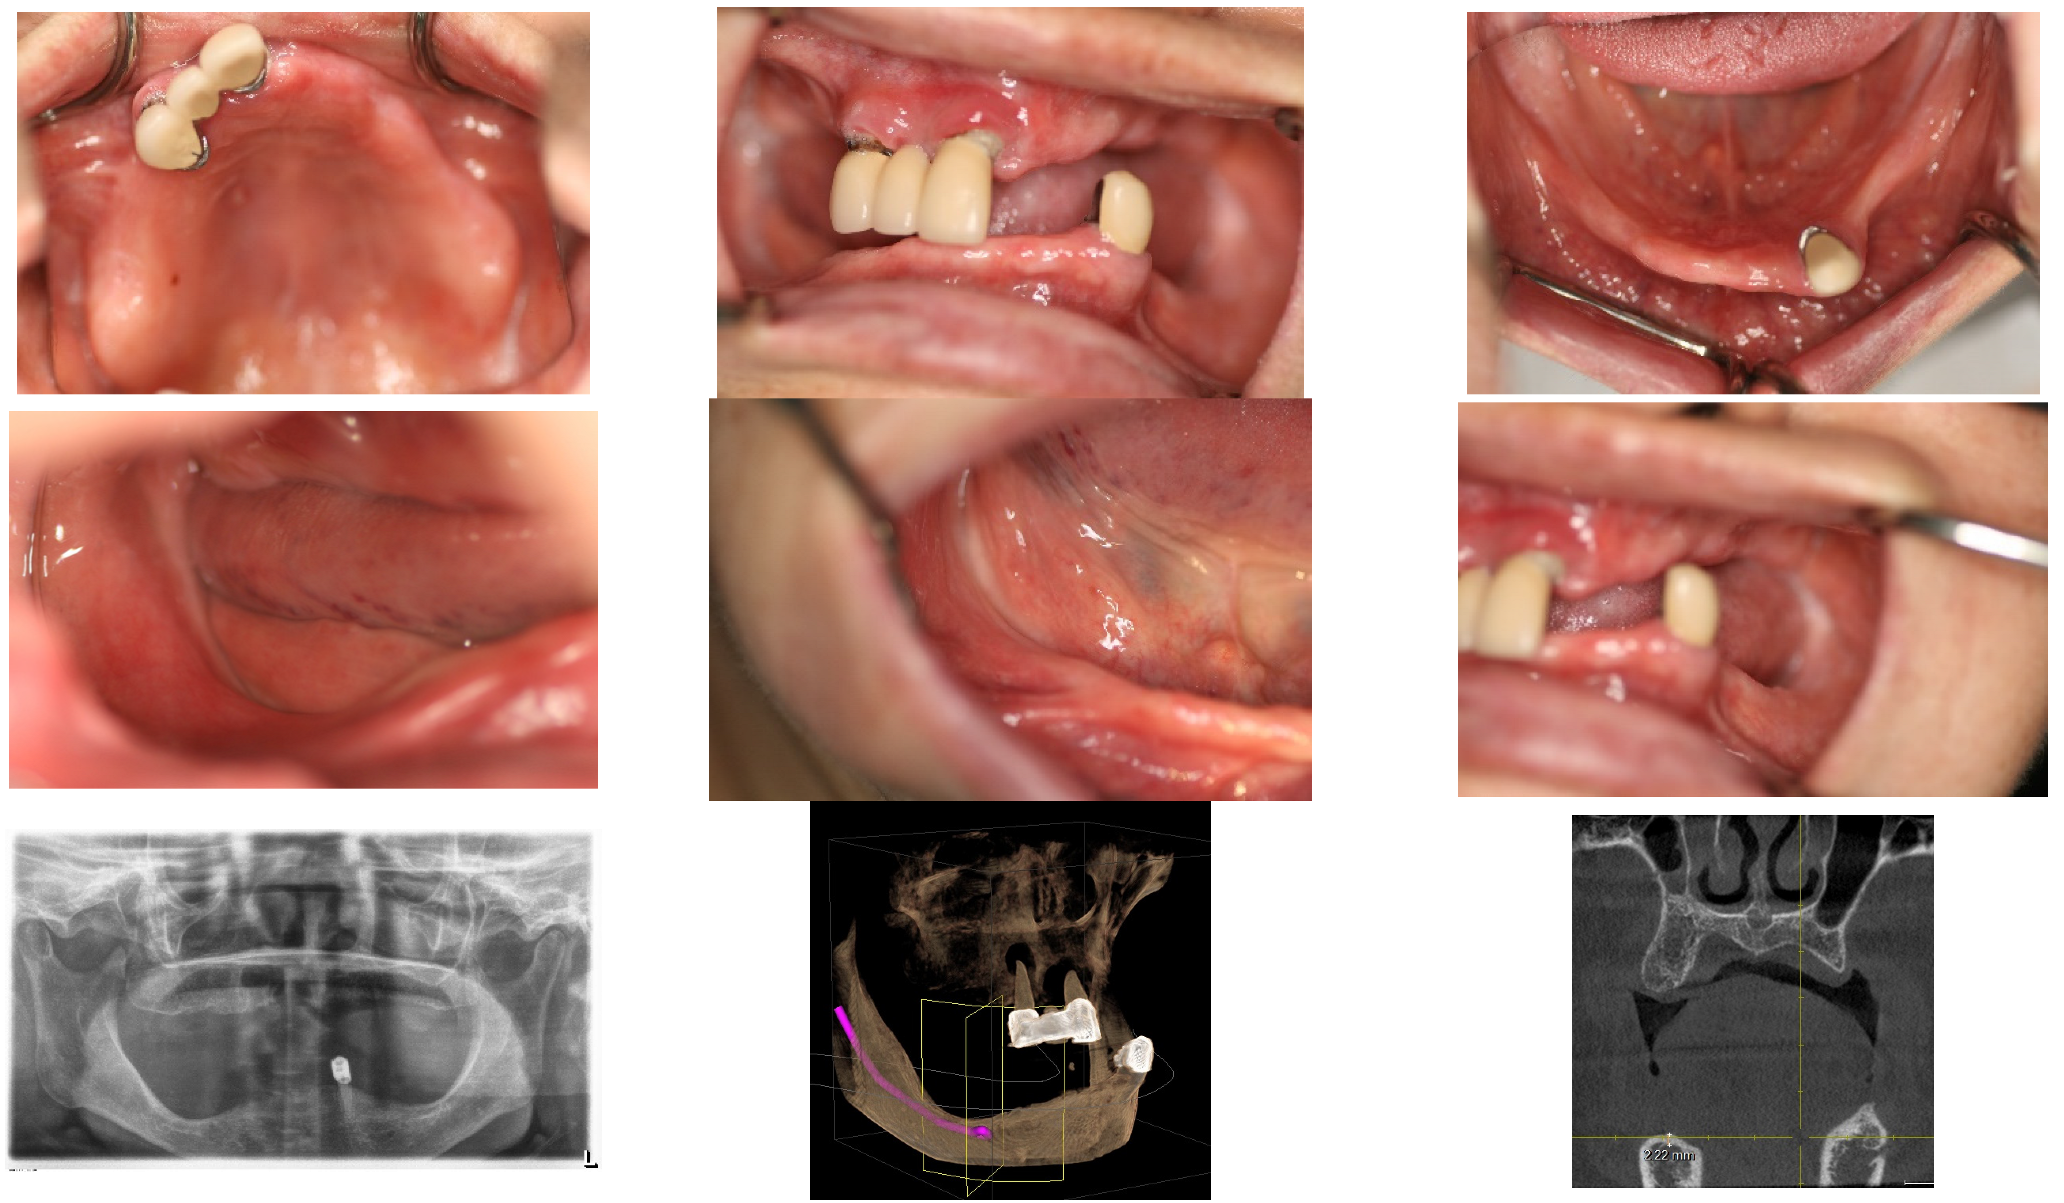

The implant restorations for the lower left posterior area were finalized on 28 September 2016, five months following the implant placements. Subsequently, the restorations for the lower right canine and first premolar were completed on 23 December 2016, seven months post-implantation. The final restorations for the lower right first molar and second molar were accomplished on 2 May 2017, six months after their implantation. This marked the conclusion of all fixed prosthesis work, spanning a total of 23 months from the beginning to the end of the treatment process (Figure 7).

Throughout all procedures, the patient tolerated the treatments well, experiencing no surgical complications such as nerve injury or wound infection. She used temporary removable dentures; however, during the critical postoperative period, which lasted about 2 months, she was advised against wearing them to avoid potential surgical complications from trauma. After this critical period, she was allowed to wear the temporary removable dentures, provided they were adjusted to alleviate pressure on the surgical site. The patient’s chewing ability was effectively restored, with occlusion being verified using Shimstock. The graft bone demonstrated stable results, showing no signs of inflammation or resorption. The implants were functioning well, with no mobility or pain reported. The patient expressed satisfaction with the outcome (Figure 8).

The patient’s masticatory function has been almost fully restored, without any discomfort or difficulties during eating. Her appearance looks natural, as though she had her natural teeth, even though she does not (Figure 9).

Figure 7. On 2 May 2017, the fixed restorations with implants for the lower arch were completed, 23 months after the commencement of the procedure, through vertical bone grafting via SITE. The completion on the right side was delayed compared to the left side due to the need for more bone regeneration, although both sides underwent the same procedure. Please compare the before-and-after treatment pictures.

Figure 9. The lower pictures were taken on 2 May 2023, and 9 January 2024, each six years and seven years after the final finishing, respectively. Please compare them with the initial pictures taken before treatment. The rehabilitation using SITE has shown stable results throughout the follow-up period.